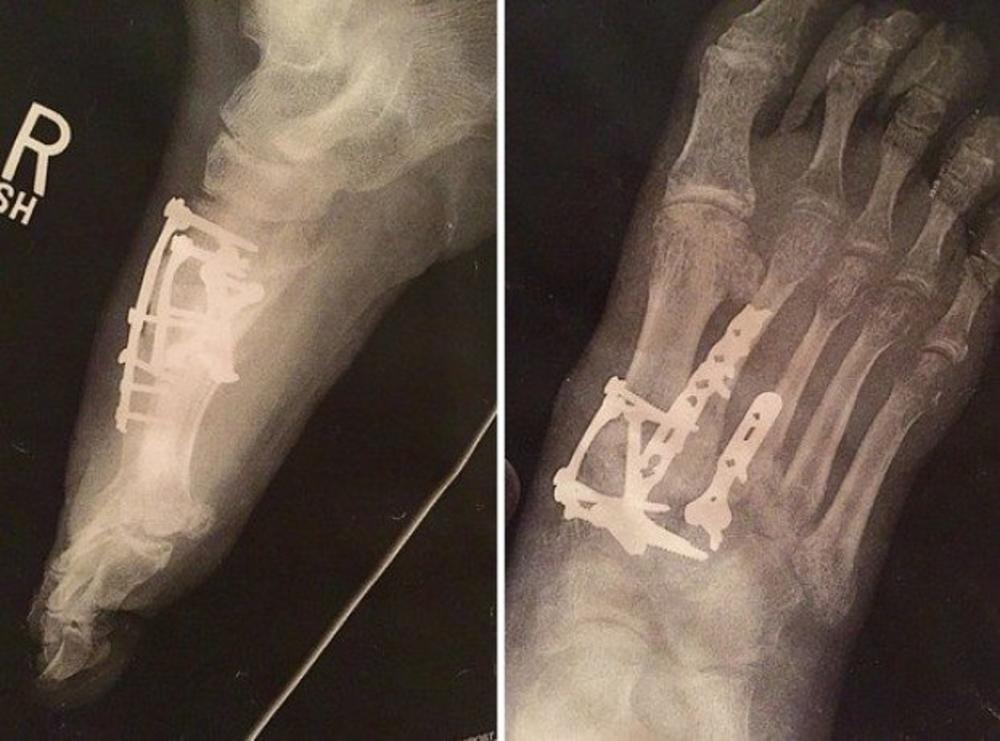

Pre nekoliko godina, čovek je slomio nogu i morao je da bude operisan.

Ugrađeno mu je 10 šrafova, kako bi ponovo mogao da hoda normalno.